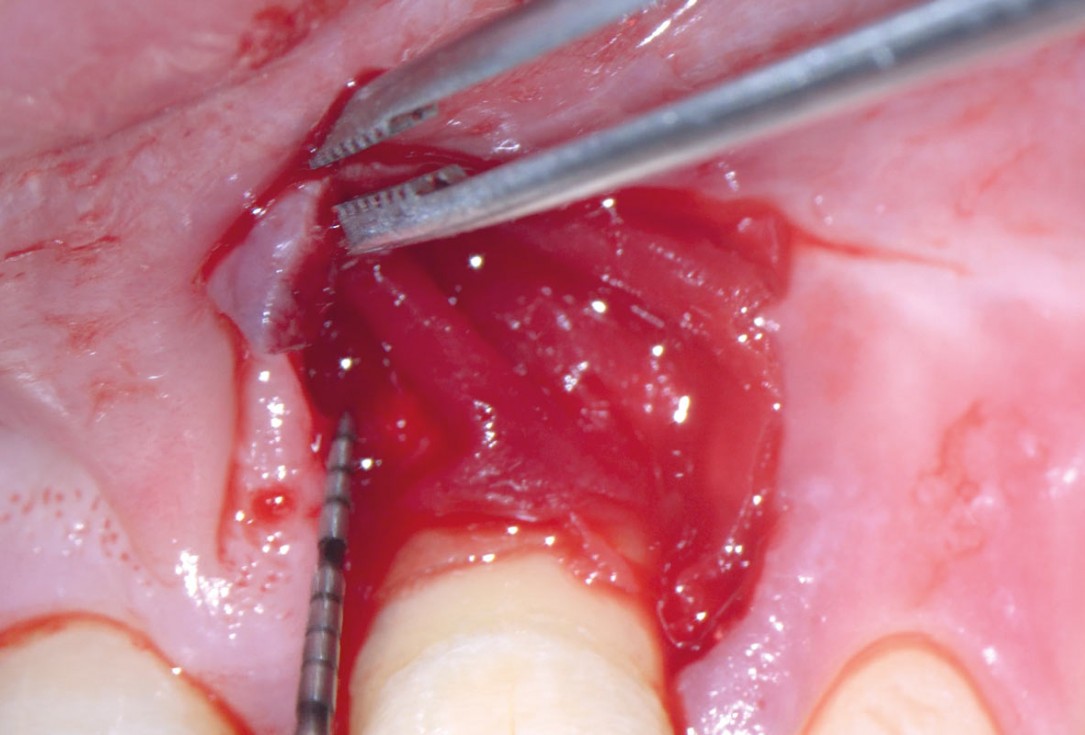

06/11 - Trimming of collprotect® membrane according to the osseous defect morphologyEntire papilla preservation technique (EPP) for the regenerative treatment of a severely compromised central incisor - Dr. S. Aslan